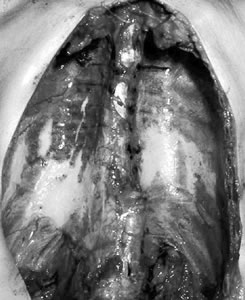

曝露の証拠│胸膜肥厚斑

![]() 肺を取り除いたところ。白いところが胸膜肥厚班 |

また健康被害ではありませんが、アスベスト曝露の証拠と考えられている胸膜肥厚斑も重要です。

これは曝露後15年くらいで、胸部のレントゲン写真やCT写真で見られる変化で、肺を包んでいる胸膜が部分的に厚く(肥厚)なったものです。これがある 人は自分では気がつかないうちにアスベスト曝露を起こしていたと考えられます。ただ、この状態ではまだ自覚症状はないので、年1回の胸部レントゲン写真、 または胸部CT写真での経過観察となります。